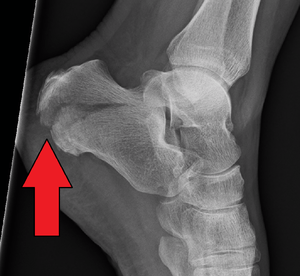

X-ray of a fractured calcaneus. | |

Calcaneal fracture is a fracture of the calcaneus. It is usually caused by a fall from height when one lands on their feet. These fractures represent approximately 2% of all fractures but 60% of tarsal bone fractures.[1] The name lover's fracture is derived from the fact that a lover may jump from great heights while trying to escape from the lover's spouse.[2]